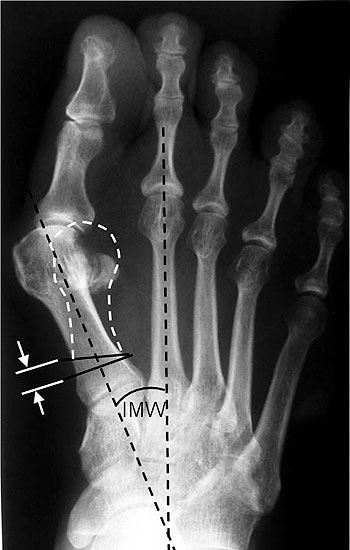

Abbildung 1

• Röntgenaufnahme des Fußes unter Belastung in d.p., schräg und seitlichem Strahlengang.

• Beurteilung des Intermetatarsalwinkels (IMA) und des distalen und proximalen Gelenkwinkels (DMAA, PMAA) (Abb. 1).

• Planung der Korrekturosteotomie: 1 mm Plattensteg korrigiert etwa 2° Intermetatarsalwinkel.